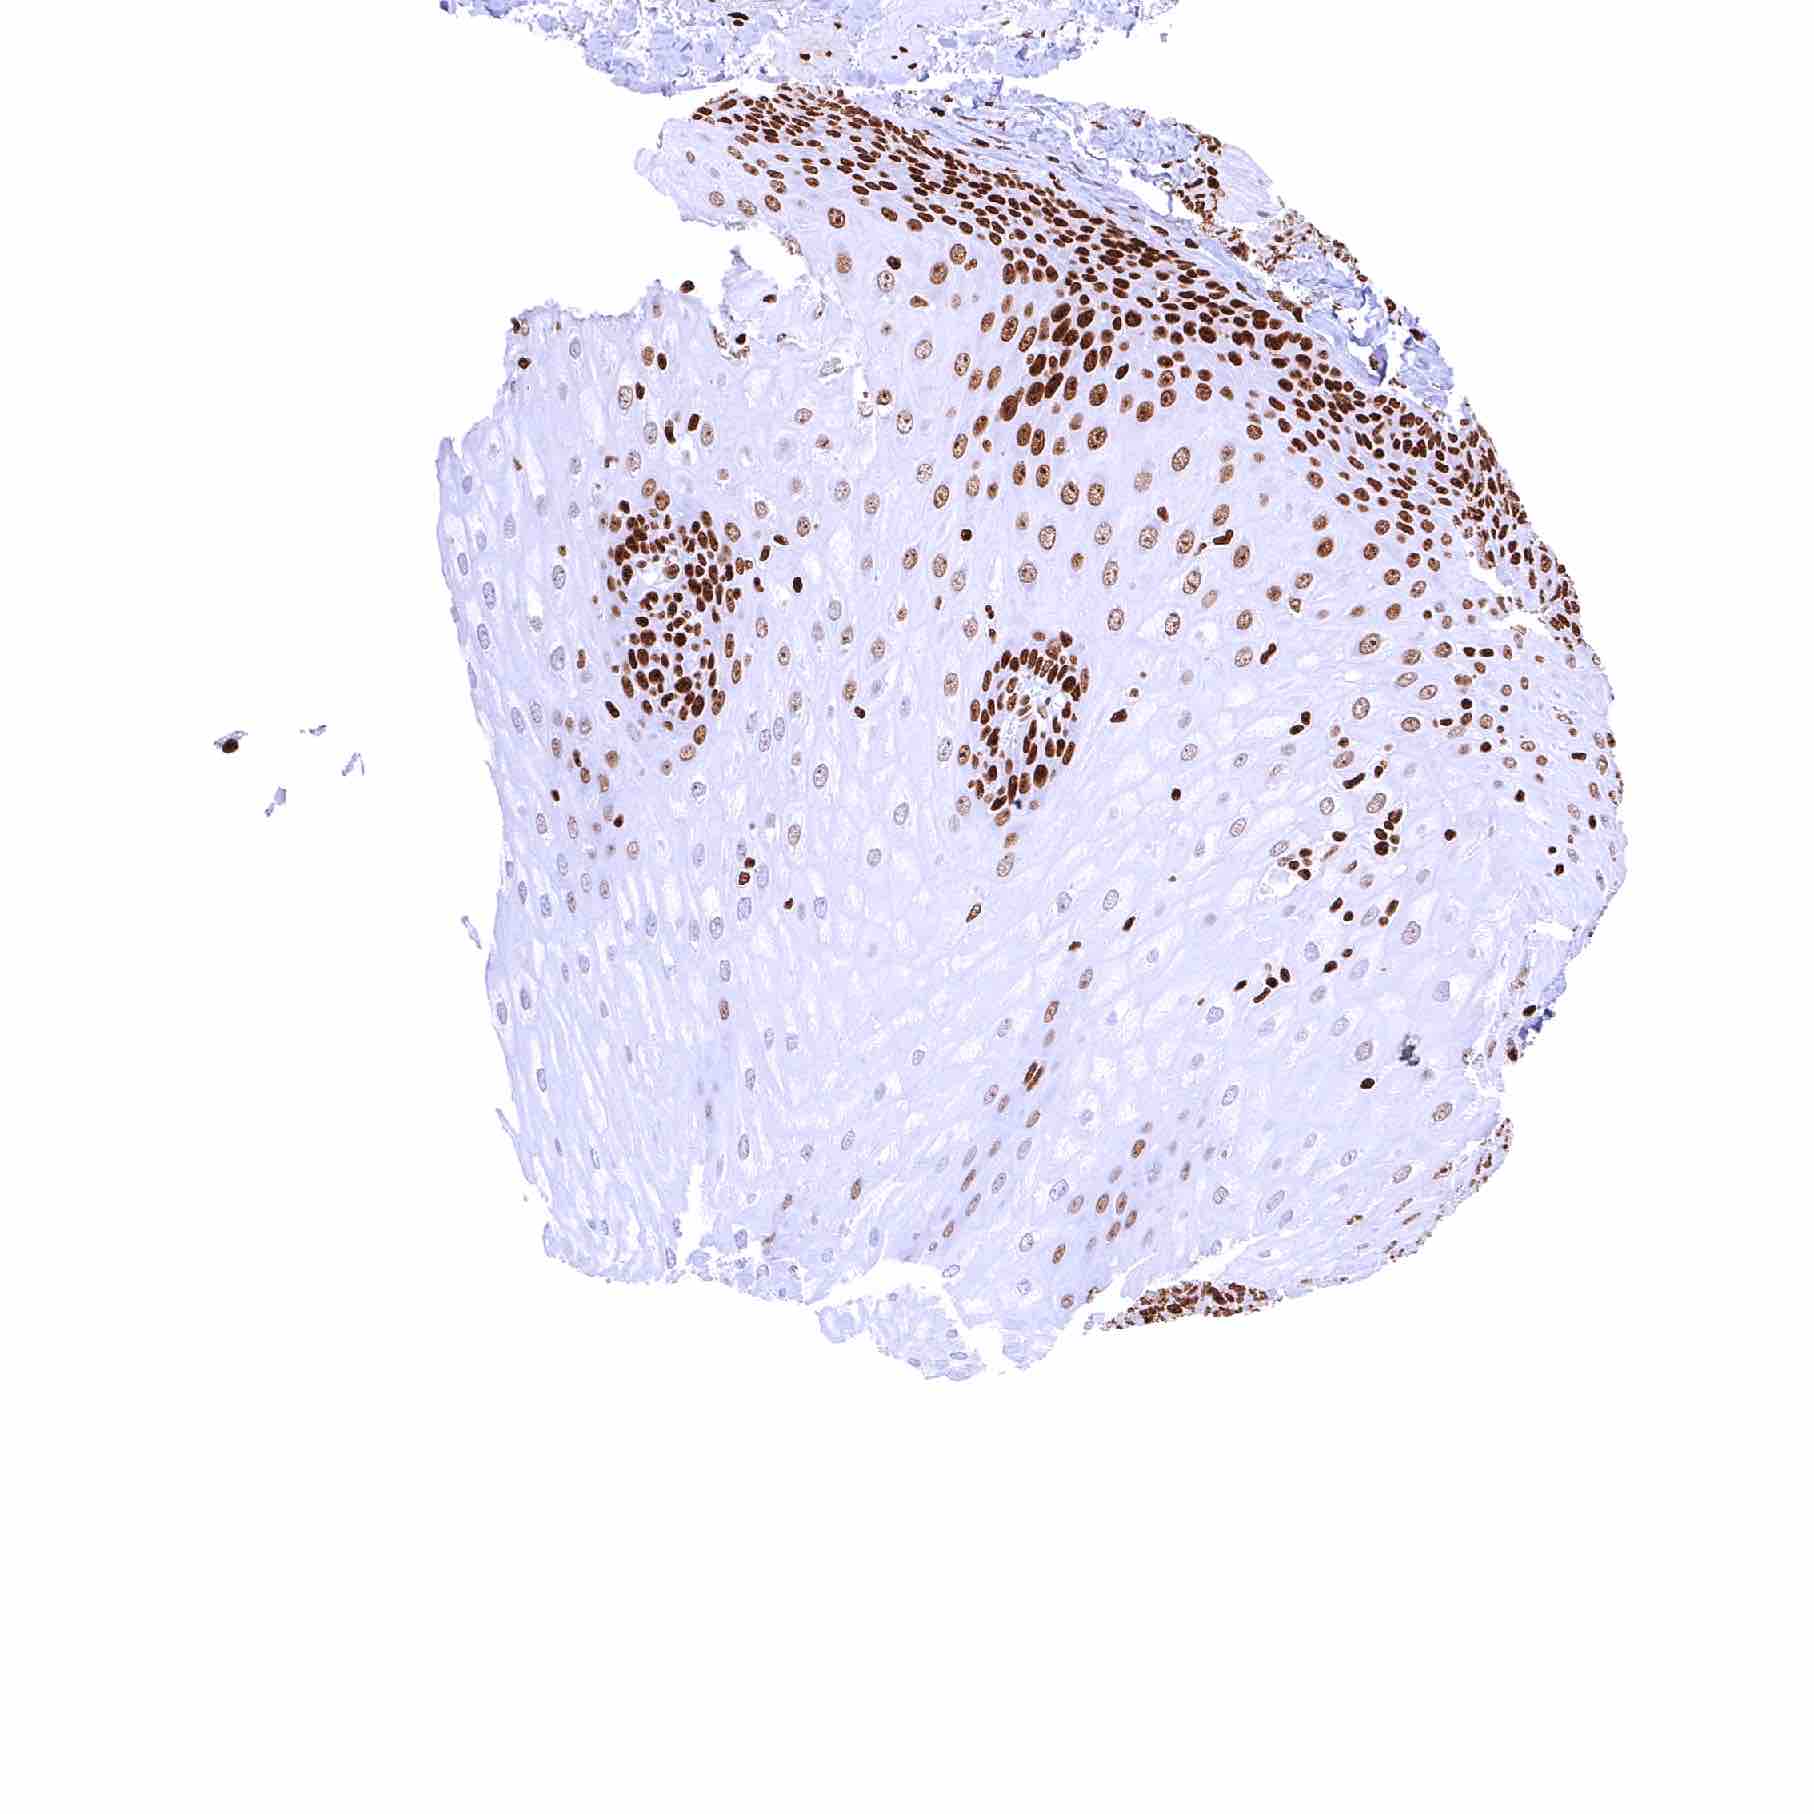

Uterus, ectocervix – Squamous epithelium shows a mild decrease of PARP1 staining intensity from the basal-suprabasal to the surface cell layers